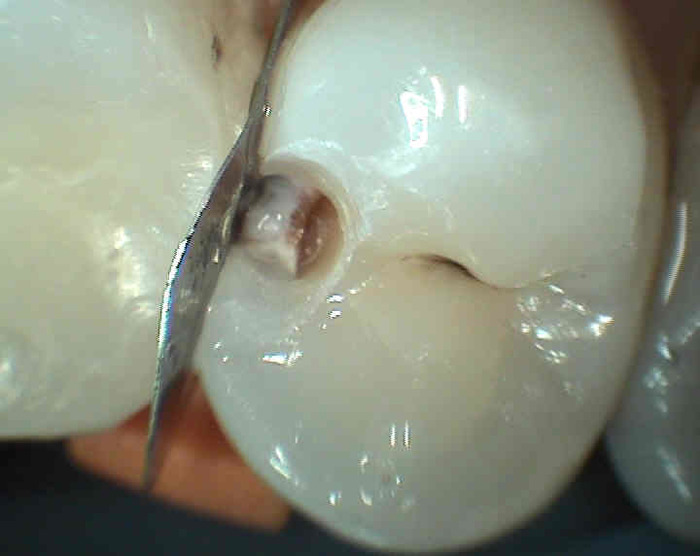

Mechanismus vzniku zubního kazu je následující: Sacharolytické bakterie (zvl.kariogenní streptokoky) rozkládají zkvasitelné zbytky potravy (jednoduché cukry) na organické kyseliny (např. mléčná) a ty rozleptávají (demineralizují, odvápňují) povrch zubní skloviny. Po průniku pod tvrdou a více mineralizovanou sklovinu do méně mineralizované zuboviny (dentinu) obsahující velké množství organických látek, mohou mikrobi přímo "konzumovat" a rozkládat tyto organické látky. V zubovině je z tohoto důvodu šíření zubního kazu rychlejší. Dosáhne -li kaz blízkosti zubní dřeně ("zubní nerv") dojde k zánětu zubní dřeně a posléze k odumření zubu. Neošetřený mrtvý zub se může později projevit zánětem ozubice.

Příznaky zubního kazu : zdrsnění povrchu zubu, ulpívání zbytků potravy, bolestivost na podráždění (chlad, sladké, někdy při skusu), v mezizubním prostoru se může trhat zubní nit ( ostré okraje kazivé dutiny).